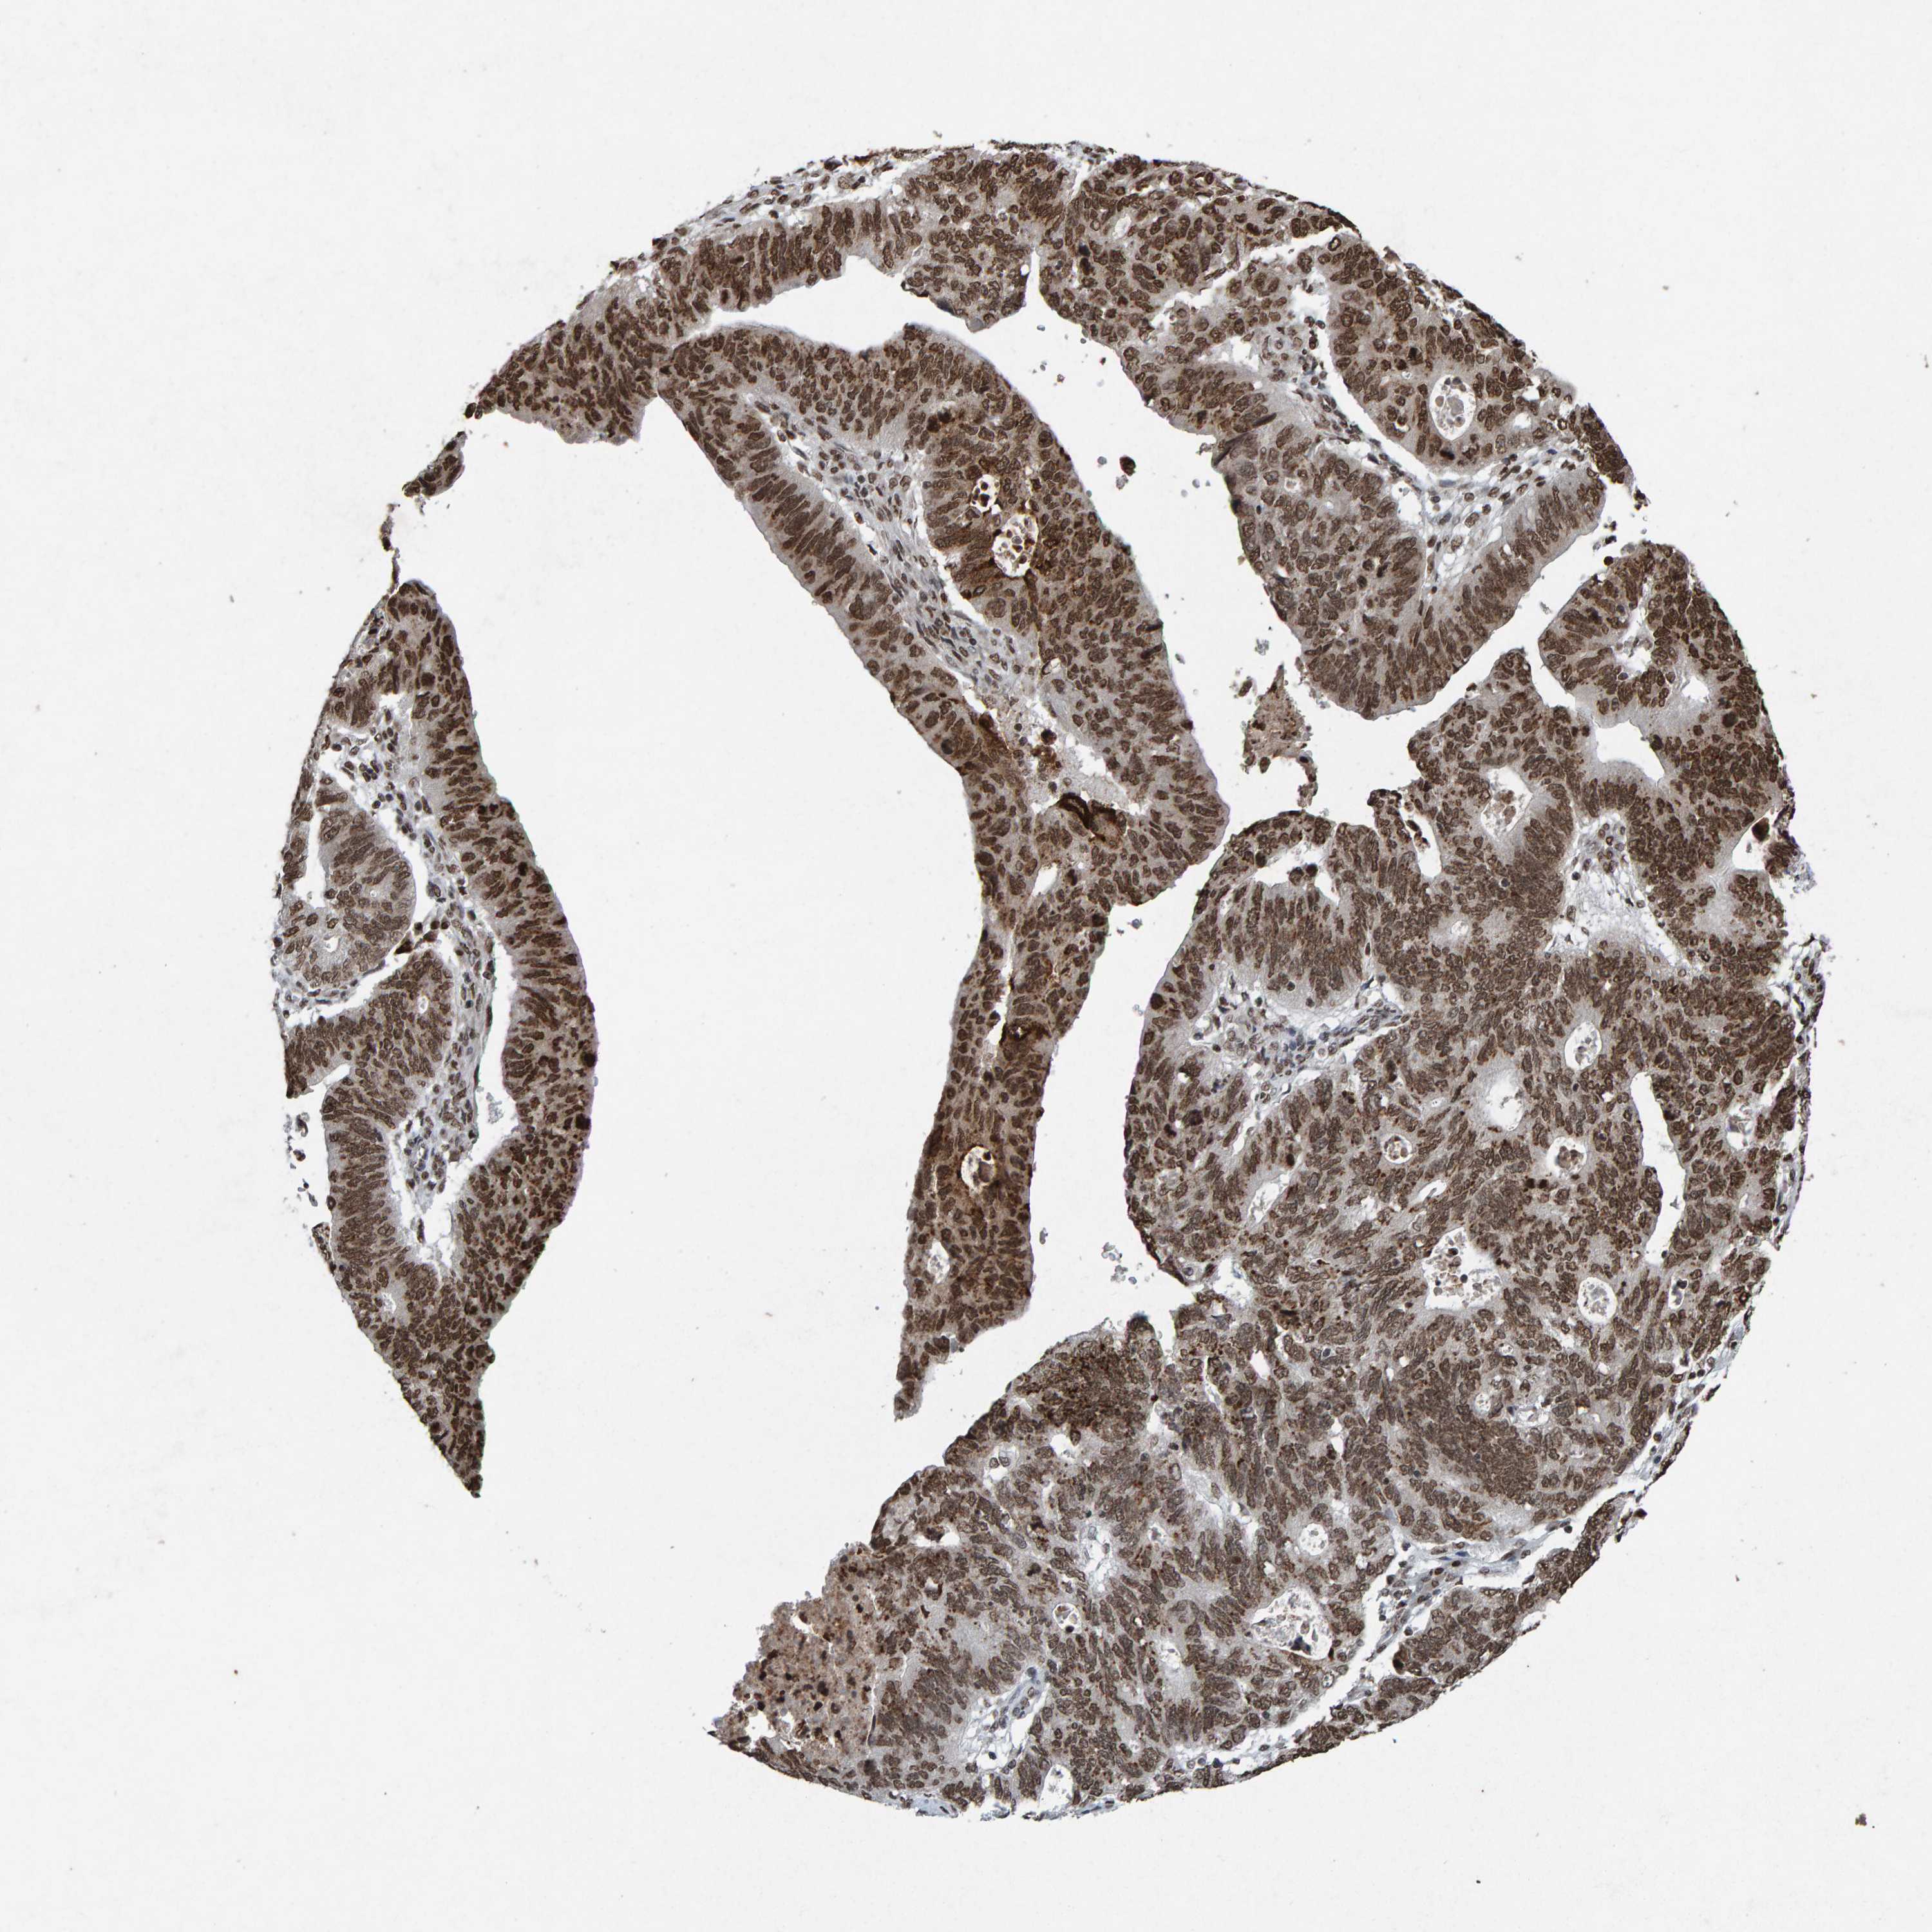

STOMACH CANCER - Protein expressioni

A mouse-over function shows sample information and annotation data. Click on an image to view it in a full screen mode. Samples can be filtered based on level of antibody staining by selecting one or several of the following categories: high, medium, low and not detected. The assay and annotation is described here.

Note that samples used for immunohistochemistry by the Human Protein Atlas do not correspond to samples in the TCGA dataset.

Antibody stainingi

Antibody staining in the annotated cell types in the current human tissue is reported as not detected, low, medium, or high, based on conventional immunohistochemistry profiling in selected tissues. This score is based on the combination of the staining intensity and fraction of stained cells.

Each image is clickable and will lead to virtual microscopy that enables deeper exploration of all samples and also displays staining intensity scores, fraction scores and subcellular localization as well as patient and tissue information for each sample.

Antibody HPA057236

Antibody CAB022549

Staining

High

Medium

Low

Not detected

Intensity

Strong

Moderate

Weak

Negative

Quantity

>75%

75%-25%

<25%

None

Location

Nuclear

Cytoplasmic/membranous

Cytoplasmic/membranous,nuclear

Adenocarcinoma, NOS

Adenocarcinoma, High grade